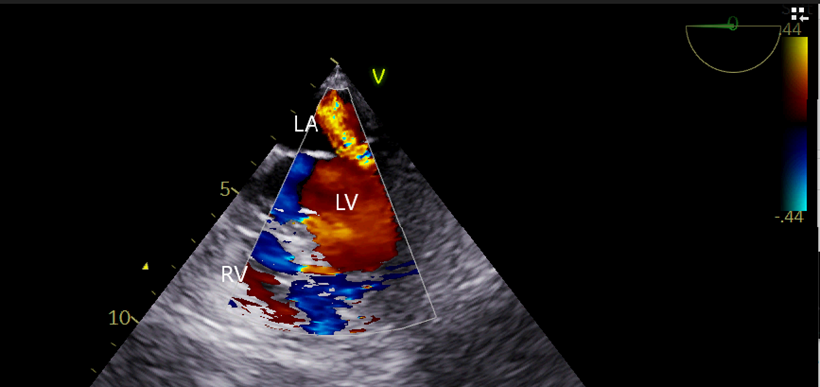

PCWP also revealed a large A wave suggestive of mitral regurgitation. A gastric tube was inserted to aspirate the stomach secretions and air and removed, and an adult TEE probe (GE, 6TC-RS, Vivid T9 v205, Norway) was inserted. Anesthesia was maintained with 60% oxygen in the air, sevoflurane 0.75- 1.5 % and vecuronium infusion (2mg/hr) with intermittent fentanyl and midazolam boluses. [9] She was positioned prone for the surgical procedure. External defibrillator pads were applied before turning the patient prone, and all resuscitation and antiarrhythmic drugs were kept ready to tackle an inadvertent arrhythmic event. The TEE was performed in the supine position and continued in the prone position with a little technical difficulty. TEE revealed an EF of 36%, fractional shortening (FS) of 17 Percent sign after inodilator support, severe MR with central jet, MR flow velocity > 5 m/sec and vena Contracta of 0.8mm(Figure 3a,b) and CO of 2.65 L/M2, mitral valve area of 4.3cm2 by planimetry, LA -31mm. (Figure 4) In addition LV basal wall aneurysmal, hypokinesia of basal, posterior and inferior LV wall, and no thrombus in LV(Figure 5a,b) and LV type 1, diastolic dysfunction (E Less-than sign)

Figure-3a: Colour Doppler of the modified ME 4 C view (0°) of TEE shows central jet of MR reaching to the roof of the LA. The vena contracta of 0.8 cm and LA size of 3.1 cm. As LA is still non-compliant (normal size) the TEE findings are suggestive of acute severe MR. it is to be noted that the tenting height was 1.2 cm, indicating significant leaflet tethering and abnormal leaflet motion during systole as a result of MI. [labelled]

ME4C – mid esophageal 4- chamber view, TEE- trans esophgeal echocardiography, LA- left atrium, MI- myocardial ischemia